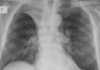

**Heart failure** Alveolar batwing shadowing Kerley B lines Cardiomegaly Upper lobe Diversion Pleural Effusion

Causes of white out on CXR

Upper zone opacification RUL = limited by horizontal fissure LUL = indistinct heart border if lingula

Middle lobe opacification Indistinct heart border

Lower lobe opacification Indistinct diaphragm border